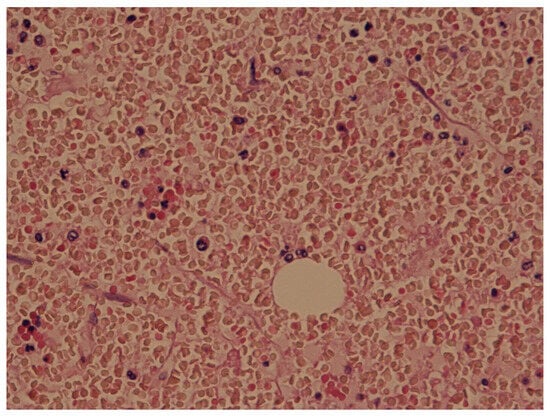

Moreover, lung samples were frozen and stained with Sudan III. The Sudan III staining of the frozen tissue colored the drops orange, revealing their fatty nature [11]. The frozen lung samples showed 20–40 emboli per field (Figure 4).

The postmortem examination of frozen lung samples showed 20–40 emboli per field, which satisfied Emson’s criteria of a moderate degree of fat embolism. When we applied volumetric analysis of fat emboli using Neri’s grading system, the samples showed moderate embolism. Hence, the cause of death was ruled as FES.

Figure 4. Lung tissue stained with Sudan III showing the multiple fat drops in orange color.